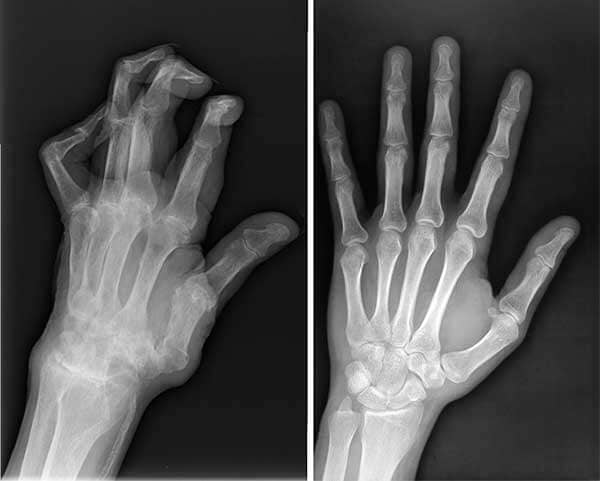

Nisam jedina kojoj je ovaj “čudesni” gel pomogao. Moj suprug Ivan također je godinama patio od bolova u rukama i imao je artritis. Odlučila sam nabaviti još Nautubone Gela i za njega. Počeo ga je koristiti sa mnom – i pomoglo mu je!

Rendgenske snimke muževljevih ruku – prije i poslije korištenja Nautubone Gela.

Muževe ruke prije i nakon tretmana Nautubone Gelom.